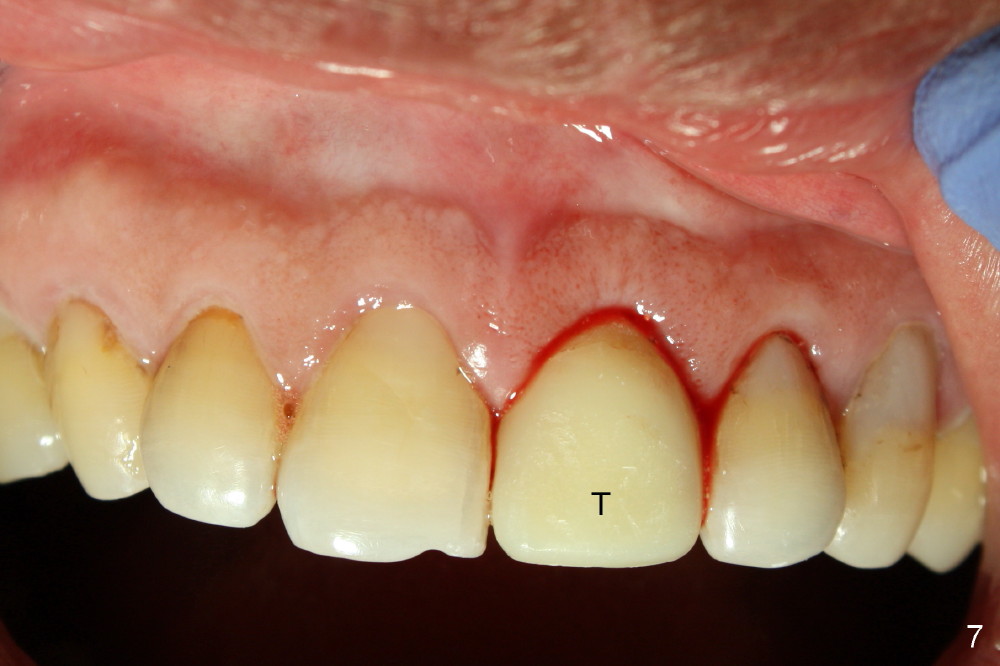

After extraction, osteotomy is made as palatally as possible so that the end of a reamer/drill (Fig.3 R) in the line of the incisal edge of the neighboring teeth. The depth of the 3.5 mm reamer is 14 mm from the crest (Fig.4 <). Next, a 5x17 mm tapered implant is placed with insertion torque > 60 Ncm (Fig.6). A 4 mm 0° unipost is permanently cemented (Fig.5: P). Finally a provisional is cemented on a temporary basis (Fig.7,8: T). There is no contact in centric or any lateral excursions.

Postop tenderness lasts for two days. The palatal swelling is unnoticeable 7 days postop (Fig.9 *, as compared to A in Fig.8). The bone remains stable around the implant (Fig.10), while the gingiva healthy around the immediate provisional (Fig.11) 5 months postop. Due to insurance limit, the permanent restoration is delayed (16 months postop, Fig.12). The patient is satisfied with the function and appearance 3 years 8 months postop (21 months post cementation, Fig.13,14). PA is taken 4 years 1 month postop (2.5 years post cementation, Fig.15). The lamina dura forms from the most coronal threads (Fig.16). Although there is no bone loss around the implant (Fig.17), metal starts to show 5 years 2 months postop (Fig.18 ^), probably related to the buccal placement, too large the implant for the site or buccal plate atrophy (Fig.19).